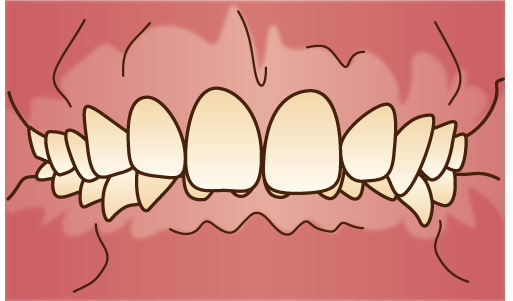

下顎前突(かがくぜんとつ)

いわゆる「受け口」と呼ばれる状態。下の歯全体、または下顎が大きく前に出てしまっている状態です。咀嚼がうまくいかず、発音にも影響が出てしまいます。

いわゆる「受け口」と呼ばれる状態。下の歯全体、または下顎が大きく前に出てしまっている状態です。咀嚼がうまくいかず、発音にも影響が出てしまいます。